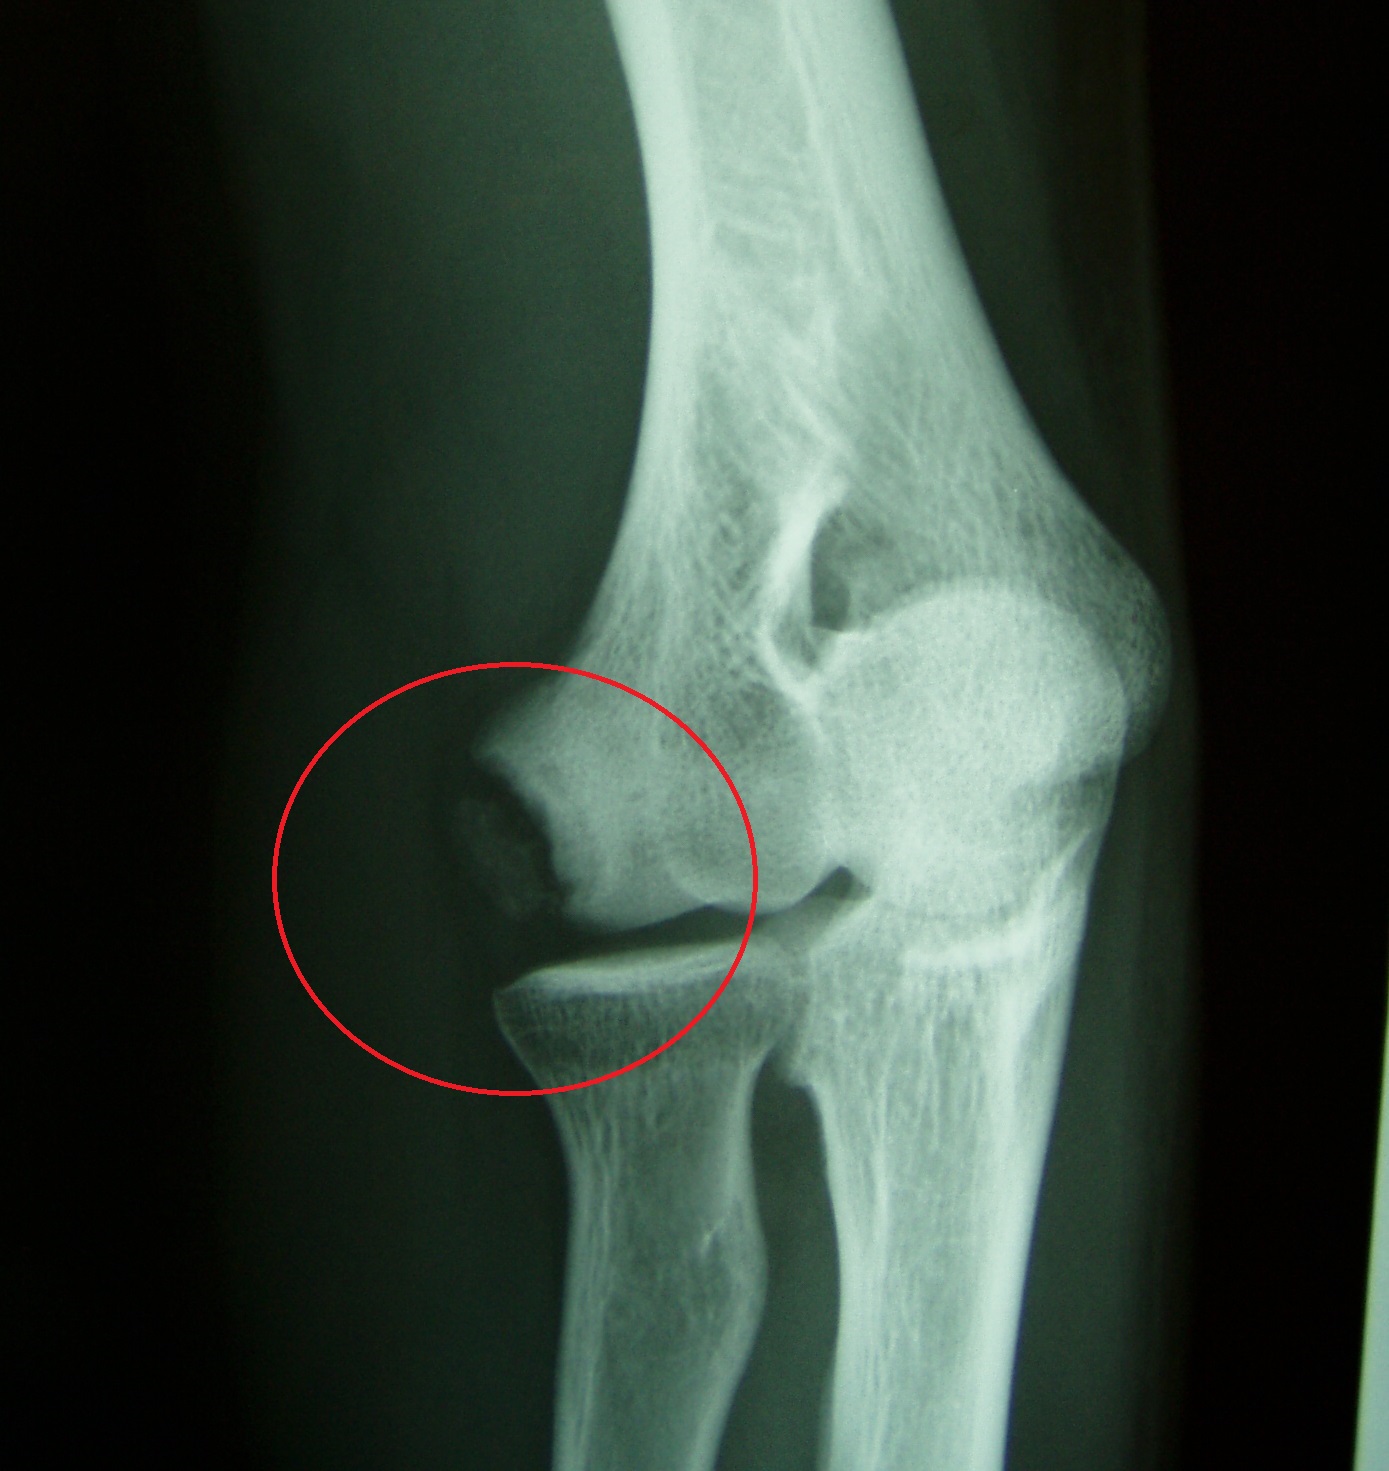

Thrower’s elbow is a sports disorder that is caused by baseball throwing, particularly overuse, which occurs in growing pitchers, and is mainly characterized by throwing pain in the throwing elbow of the medial side (Fig. 1), the outer side (Photo 1), and the elbow head (Photo 2). Symptoms often develop gradually and become chronic, so attention should be paid to elbow pain. The acceleration phase (acceleration) of throwing movements takes place in elbow flexion, valgus, and forearm supination. In the medial type, traction is exerted by the pronator flexor in throwing on the inside of the elbow, stretching the pronator muscles, the medial collateral ligaments, and the ulnar nerve, causing micro-damage inside the elbow. In severe cases, the medial epicondyle of the humerus develops avulsion fractures due to traction. In the lateral type, pressure is applied to the capitulum of the humerus and radius on the lateral side of the elbow, resulting in osteochondritis dissecans, with bone necrosis, defects, and loose bodies. The posterior type is in an elbow extension position during deceleration (follow-through), and traction forces are applied to the olecranon of the ulna, resulting in changes such as avulsion and stress fractures.

Photo 1 Lateral type: free bone in the capitulum of the humerus

These symptoms can be accompanied by bony changes on X-ray. In the medial type, bone thickening of the medial epicondyle of the humerus, epiphyseal line separation, and free bone in the pronator region are observed; in the lateral type, bone deformation, defect, and a free bone fragment of the capitulum of the humerus and head of the radius are observed; and in the posterior type, fissure fracture and stress fracture of the olecranon of the ulna are observed.